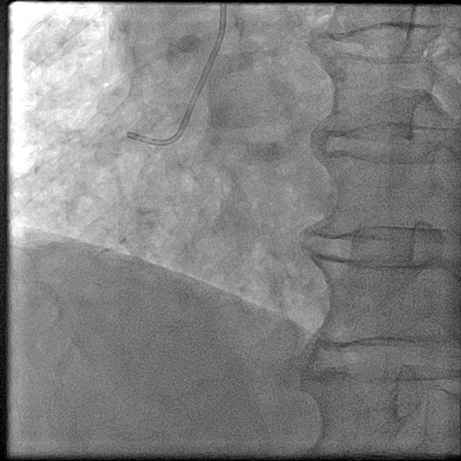

【临床病例】心肌梗死、心力衰竭患者心室率控制不佳怎么办?--新型If通道阻滞剂的应用

文章来自:中山二院心脏病MDT 叶伟斌 张坤